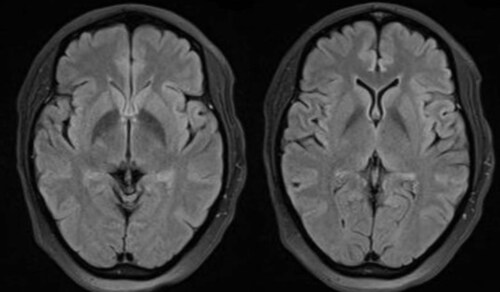

New-onset refractory status epilepticus following the ChAdOx1 nCoV-19 vaccine

"Healthcare providers...